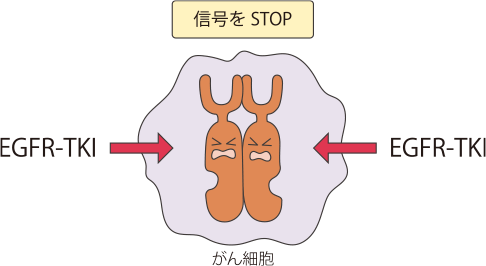

EGFRは、がん細胞が増殖するのに必要な信号を細胞内に伝えるタンパク質で、がん細胞の表面にたくさん発現していることが多く、このタンパク質からの信号が細胞内に伝わるとがん細胞が増殖します。

非小細胞肺がんの細胞の表面にはEGFR(上皮成長因子受容体)と呼ばれるタンパク質がたくさん発現しており、このEGFRは、外部から刺激を受けると、がん細胞が増え続ける(増殖)のに必要な信号を細胞内に伝える役割を担っています。

非小細胞肺がんにはこのEGFRを構成している遺伝子の一部(チロシンキナーゼ部位)に変異が認められる腫瘍があることがわかっています。

変異の中にはEGFRのスイッチを常時ONにして、がん細胞の増殖を促すものもあります。

肺がんの治療薬であるEGFRチロシンキナーゼ阻害薬(EGFR-TKI)は、EGFR遺伝子変異のある患者さんで効果の高い薬剤といわれています。また、非小細胞肺がんの扁平上皮がんでは、EGFR遺伝子変異の発現頻度がとても低いことがわかっています。このため、扁平上皮がん以外の組織型の非小細胞肺がん患者さんは、薬物療法を開始する前にEGFR遺伝子変異検査をおこない、陽性の場合にEGFR-TKIを使うことが推奨されています。